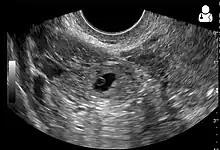

An ultrasound showing a gestational sac with fetal heart in the fallopian tube has a very high specificity of ectopic pregnancy. Transvaginal ultrasonography has a sensitivity of at least 90% for ectopic pregnancy.[4] The diagnostic ultrasonographic finding in ectopic pregnancy is an adnexal mass that moves separately from the ovary. In around 60% of cases, it is an inhomogeneous or a noncystic adnexal mass sometimes known as the "blob sign". It is generally spherical, but a more tubular appearance may be seen in case of hematosalpinx. This sign has been estimated to have a sensitivity of 84% and specificity of 99% in diagnosing ectopic pregnancy.[4] In the study estimating these values, the blob sign had a positive predictive value of 96% and a negative predictive value of 95%.[4] The visualization of an empty extrauterine gestational sac is sometimes known as the "bagel sign", and is present in around 20% of cases.[4] In another 20% of cases, there is visualization of a gestational sac containing a yolk sac or an embryo.[4] Ectopic pregnancies where there is visualization of cardiac activity are sometimes termed "viable ectopic".[4]

A "blob sign", which consists of the ectopic pregnancy. The ovary is distinguished from it by having follicles, whereof one is visible in the field. This patient had an intrauterine device (IUD) with progestogen, whose cross-section is visible in the field, leaving an ultrasound shadow distally to it.